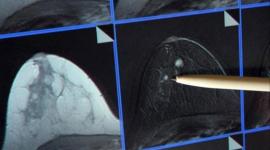

دواء رخيص يحسّن علاج سرطان الثدي

11 يوليو 2015